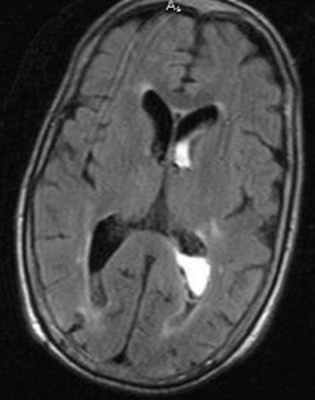

МРТ головного мозга. Т1-взвешенная аксиальная МРТ. Субдуральная гематома. Цветовая обработка изображения.

МРТ головного мозга. Аксиальная Т2-взвешенная МРТ. Кровоизлияние в мозжечок.

МРТ головного мозга. Аксиальная МРТ типа FLAIR. Аневризма и САК, внутрижелудочковое кровоизлияние.

МРТ головного мозга. Аксиальная Т2-взвешенная МРТ. Подострая субдуральная гематома.

КТ. Эпидуральная гематома.

МРТ головного мозга. Аксиальная Т2-взвешенная МРТ типа FLAIR. Внутрижелудочковое кровоизлияние.

МРТ головного мозга. Корональная Т1-взвешенная МРТ. Апоплексия макроаденомы гипофиза с кровоизлиянием.